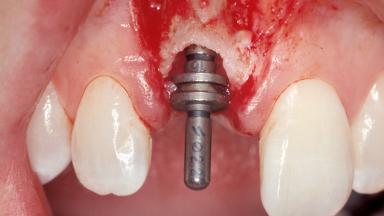

Immediate Placement of an Implant in a Maxillary Right Central Incisor Site

A 30-year-old female patient was referred to the office for the treatment of tooth 11. Her chief concern at the initial visit was to inquire, “Why is my tooth pink?” Upon clinical examination, it was determined that tooth 11 had a previous history of trauma and that the clinical crown had become noticeably pink in color as a result of internal resorption. This diagnosis was confirmed radiographically, indicating a large radiolucency involving the central and distal portions of the clinical crown. It was determined that restoration of this tooth was not possible, and that extraction was indicated. The presence of a mid-line diastema, which the patient wanted to reproduce, directed the treatment plan for tooth replacement utilizing a dental implant.

| Placement Protocol | Immediate implant placement |

| Socket Morphology | Single-root socket |